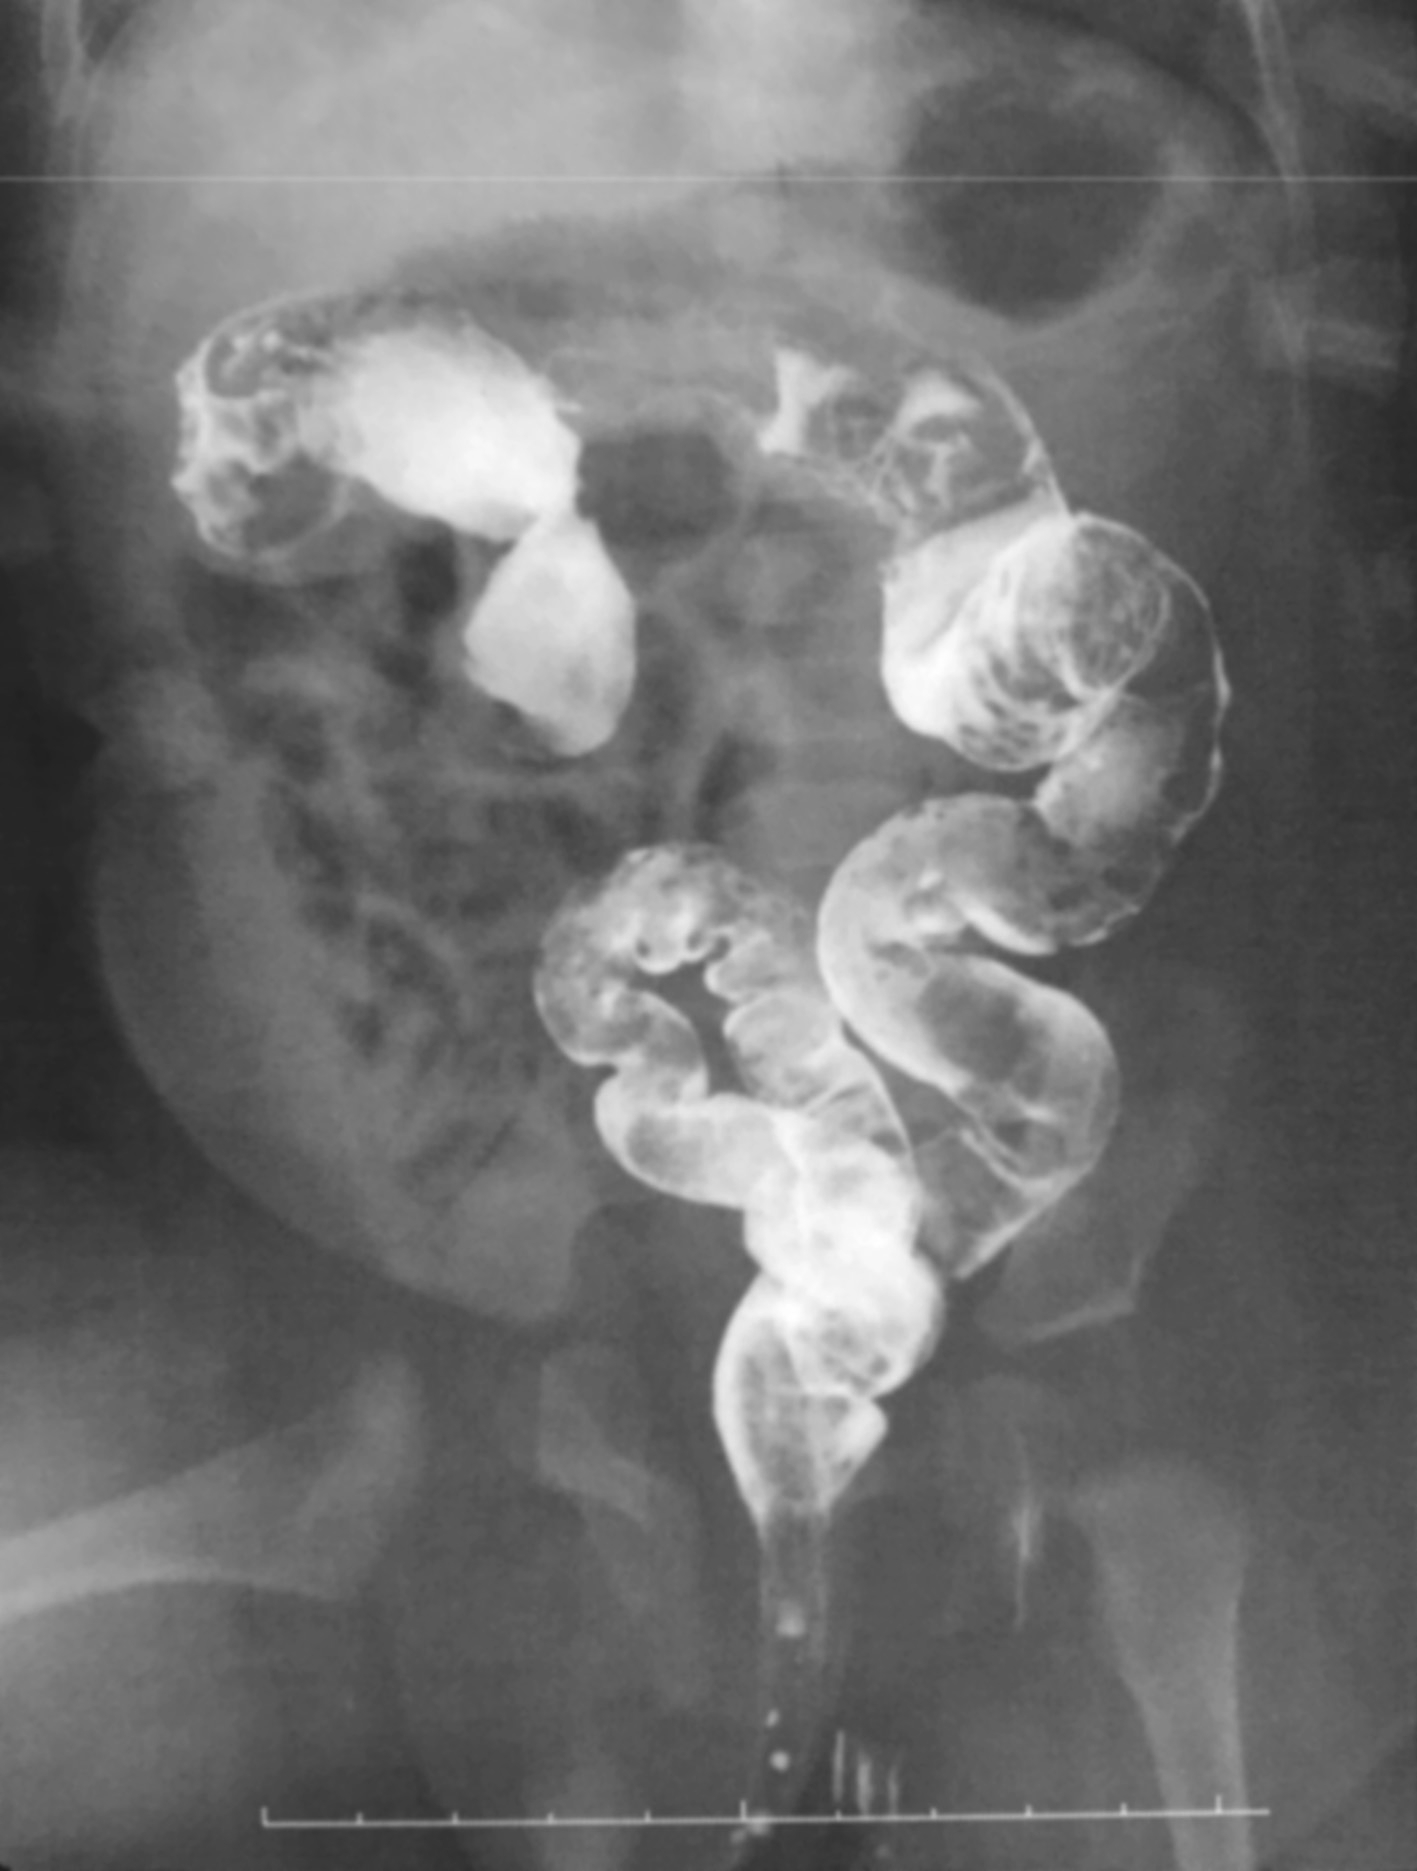

HD患儿立位腹部平片多表现为低位性肠梗阻,腹部可见多发液平、肠管积气、结肠扩张等。这种积气的肠段往往从盆腔开始,顺乙状结肠上行,而其远端则一直未见气体(图3-1)。新生儿时期结肠扩张不如儿童明显,单靠平片诊断比较困难,必须结合病史及其他检查(图3-2)。

图3-1 先天性巨结肠症腹部平片

乙状结肠积气,扩张明显,直肠未见扩张。